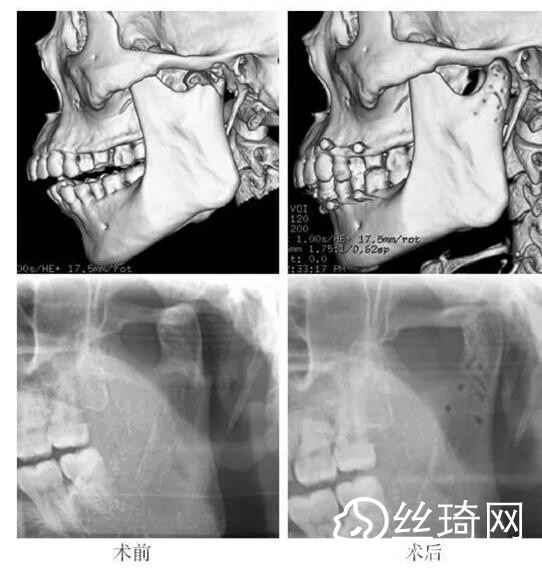

在106側(cè)中,髁突高位矢狀骨折46側(cè),中位髁頸骨折26側(cè),低位髁頸下骨折34側(cè)。髁突高位矢狀骨折及中位髁頸骨折均經(jīng)耳屏前徑路復(fù)位;34側(cè)低位髁頸下骨折中,經(jīng)耳屏前徑路復(fù)位13側(cè),頜下徑路復(fù)位19側(cè),頜后徑路復(fù)位1側(cè),穿腮腺徑路復(fù)位1側(cè)。髁突高位矢狀骨折復(fù)位后以1~2枚可吸收長螺釘固定(圖1)[3],采用的可吸收內(nèi)固定系統(tǒng)為BioSorb(ConMed Linvatec,芬蘭)、Inion OTPS(Inion,芬蘭);規(guī)格:直徑2 mm,長度15~20 mm。中位髁頸骨折及低位髁頸下骨折多以2塊可吸收板固定(圖2)[3],個別病例以1塊或3塊可吸收板固定,采用的可吸收內(nèi)固定系統(tǒng)為BioSorb(ConMed Linvatec,芬蘭)、Grand Fix(Gunze,日本)、Inion OTPS(Inion,芬蘭);規(guī)格:直4孔板,孔徑 mm或2.5 mm,長度21~35 mm,螺釘直徑 mm或2.5 mm,長度7~10 mm??晌蔗敯宓氖中g(shù)操作采用專用器械工具盒,并遵照廠家操作指引進行。

82例髁突骨折患者,術(shù)后隨訪6個月至3年,平均年。所有患者術(shù)后未訴明X不適,面型基本對稱,面部肌肉運動正常,咬合對位良好,開口度~4.2 cm,平均(±)cm。3例患者開口型輕度偏斜,均為髁突高位骨折,其中2例為粉碎性骨折行骨折碎片摘除,1例為矢狀骨折,以可吸收螺釘固定后,創(chuàng)口感染,隨后行局部清創(chuàng)并取出髁突骨折片及可吸收螺釘,創(chuàng)口愈合良好。96側(cè)髁突骨折中,2例髁頸下骨折術(shù)后復(fù)查CT顯示輕度移位,但患者無功能障礙,持續(xù)觀察,未做特殊處理。其他患者未見明X排斥反應(yīng)及并發(fā)癥。